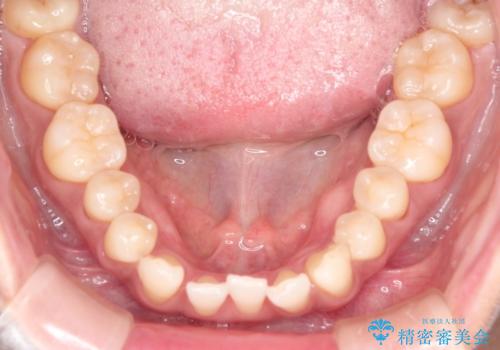

前歯のがたつきと隙間の矯正 インビザラインにて

- 上顎の前歯のがたつきと、下の前歯の隙間を主訴に来院されました。

下の前歯が先天的に欠損していました。

上顎の歯と歯の間をわずかに削りスペースを作り、ガタガタの改善し、下顎の前歯は隙間を閉じる計画としました。

非常に協力的な患者様でしたので、早期に治療が終了することができました。